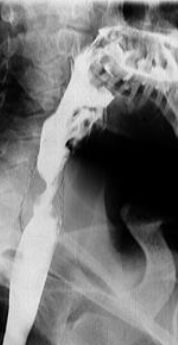

Diverticul medioesofagian complicat cu fistulă

Diverticul medioesofagian complicat cu fistulă esobronșică